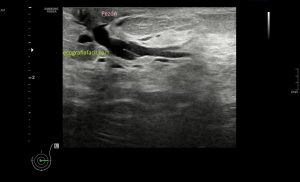

Al explorar la parte interna del muslo, en la zona donde nos señala la paciente encontramos esto…

Rotura

Una imagen de semiología heterogénea que me pareció una rotura fibrilar importante afectando al interior de un músculo de localización interna del que en un primer momento sospeché que podía ser el vasto interno, pero la anatomía no cuadraba, demasiado interno, demasiado cerca de los vasos…

Después de estudiar la rotura en dos planos (imagen 1 y 2) y medirla (imagen 3 y 4), documentarla bien referenciándola con la anatomía locorregional, incluidos los vasos (imagen 5), decidí seguir el recorrido del músculo partiendo desde la rotura siguiendo las instrucciones que me había comentado la paciente y me dí cuenta que el músculo afectado cruzaba el muslo desde el tercio proximal del muslo, en la cara anterior de la cadera (en su porción más superficial) hasta la cara interna de la pierna…en concreto desde la espina iliaca antero superior y terminando en la inserción de la Pata de Ganso.